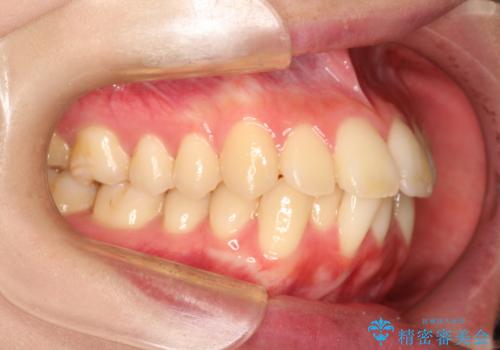

出っ歯を改善した後に真っ白な歯に 矯正歯科治療と審美歯科治療